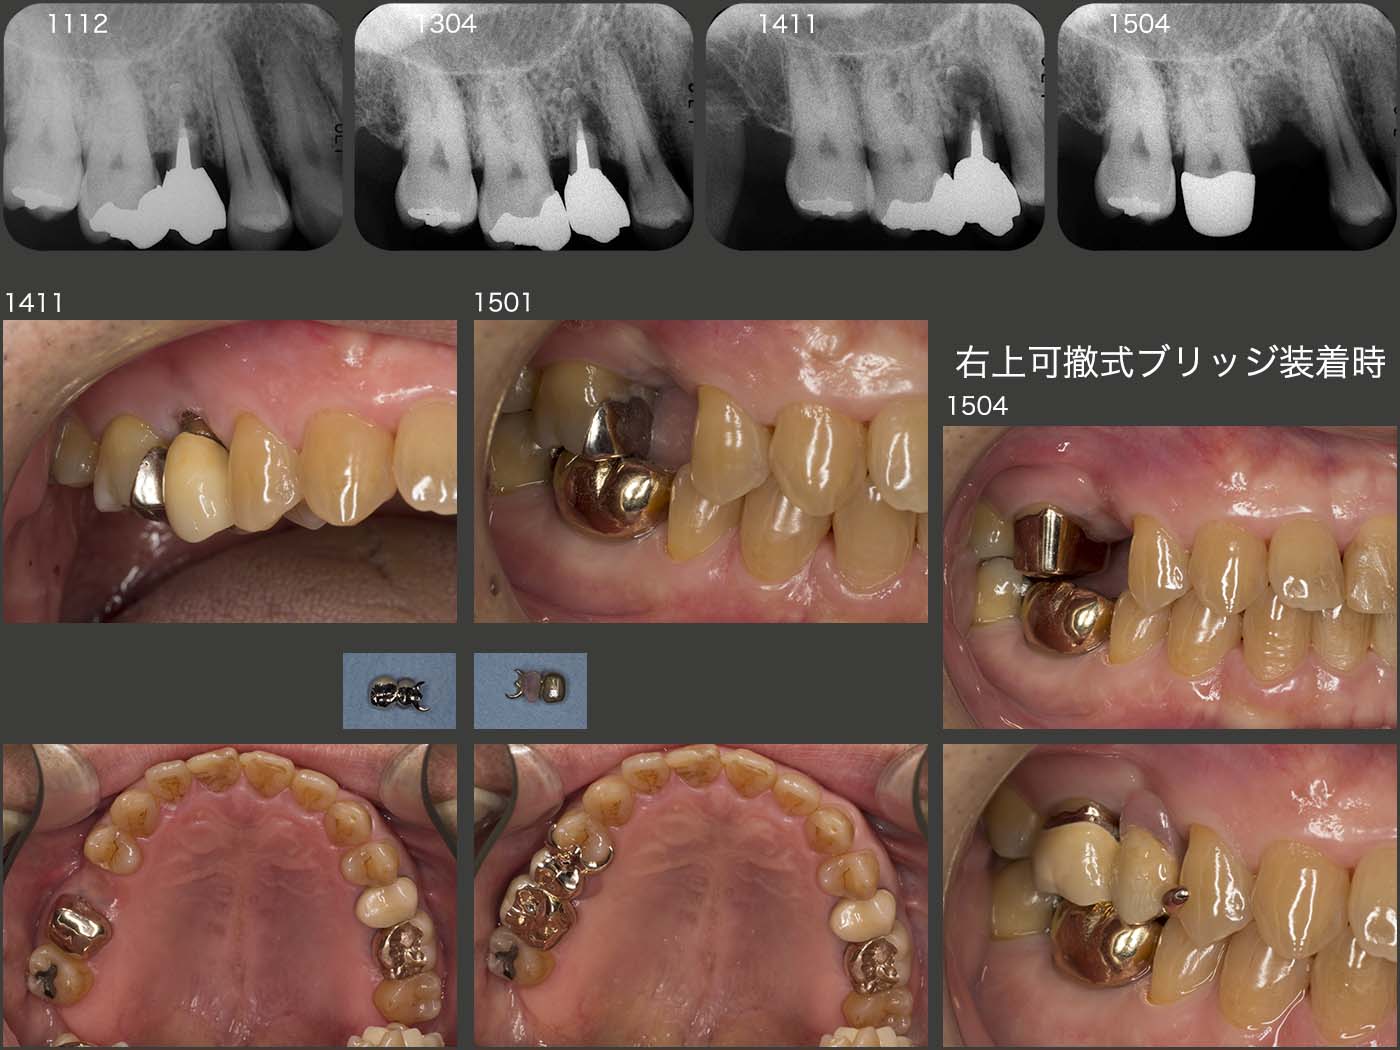

2014年11月,07年に再植した右上5の動揺が著しくなり,保存不可能となった.11年12月のデンタルX線写真からみてとれるように,炎症性吸収像がみられたが,それが3年かけて拡大してしまった.穿孔部の封鎖がよくなかったことが原因と思われるが,稚拙な手技に反省する次第である.

右上5の補綴に関しては,右上4がバージントゥースであることから,切削せず,右上6にコーヌス冠を用いた可撤式のブリッジを製作した.

2018年1月の状態.右下6は移植後13年,左上6は移植後6年経過している.特に左上6は,移植時頰側に全く歯槽骨がなかったので大変心配したが,今のところ順調に経過している.本当に,歯根膜の凄さに今更ながら驚かされる.

2018年1月,可撤式ブリッジ装着時の状態.04年5月の初診時から合計4本歯根破折を起こしている.当然すべて無髄歯であることから,やはり抜髄しないことが大切である.当然,移植歯も無髄歯であるから決して安心はできない.しかし,患者さんは今年定年を迎え,仕事中のTCHも減ることから,この先は安定するのではないかと期待している.